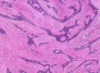

what is the hallmark of the lobular variant of invasive (infiltrating) breast carcinoma

dyscohesive infiltration tumor cells with no tubular formation